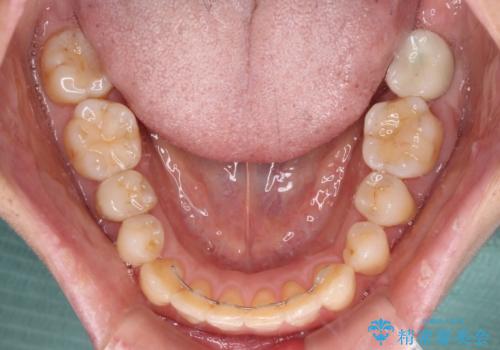

後戻りの程度は軽度であったため、インビザライン・ライトを用いて歯列を整えました。

再度後戻りするリスクを最小限に食い止めるため、下顎前歯の舌側を細いワイヤーで固定しました。